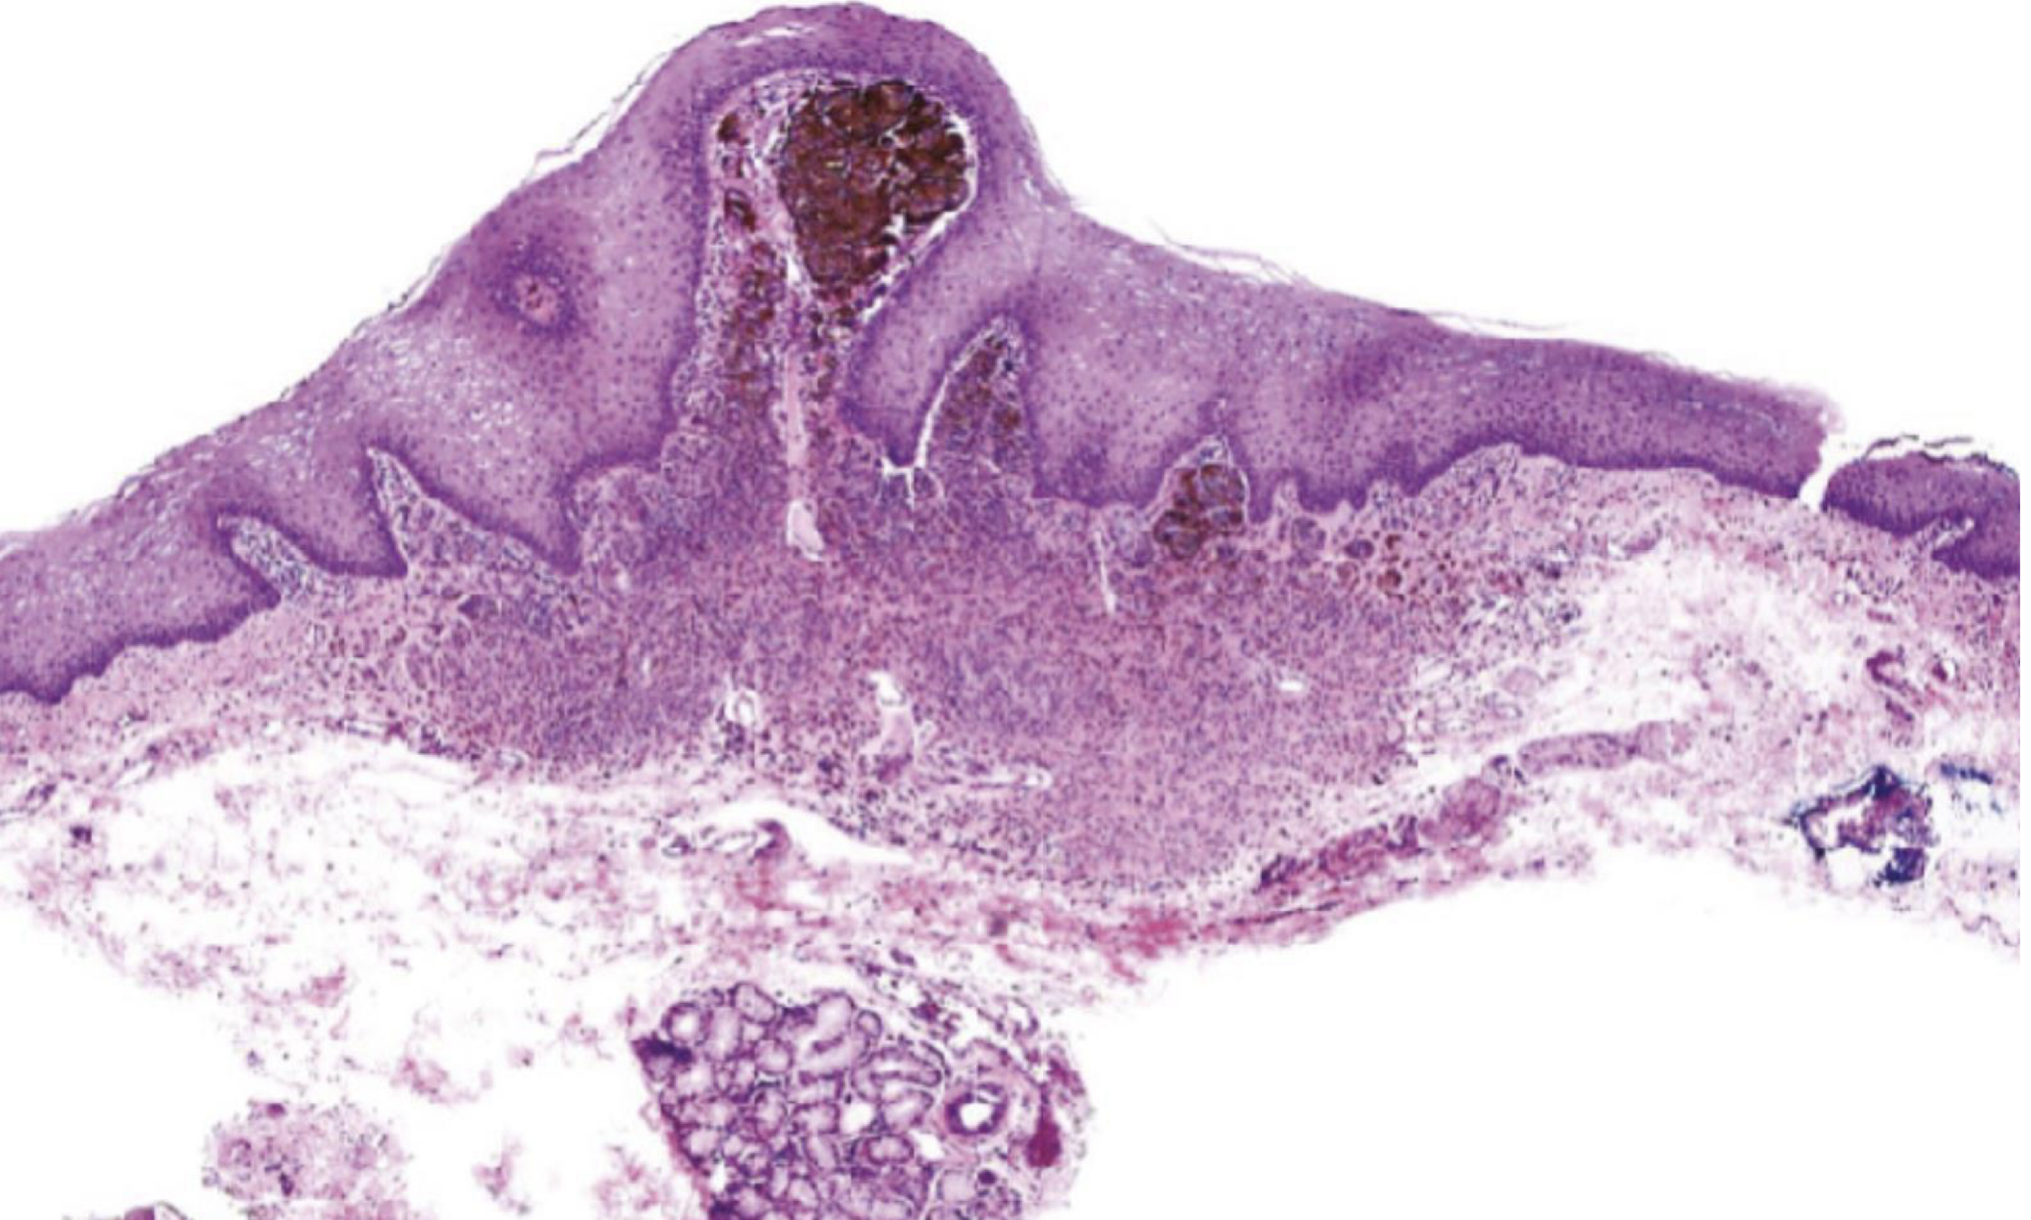

which melanocytic nevus histopathological features?

Unencapsulated proliferation of nevus cells, organized in theques

Lack dendritic processes of melanocytes

Migrate from junctional to compound to intradermal

acquired melanocytic nevus

intramucosal nevus, (unique nevus cells)

nest of melanocytes, unique

Type B to Type C morphology is a key characteristic of benign nevi and a sign of normal cell maturation, which helps pathologists distinguish them from melanoma, where this organized maturation process is typically lost